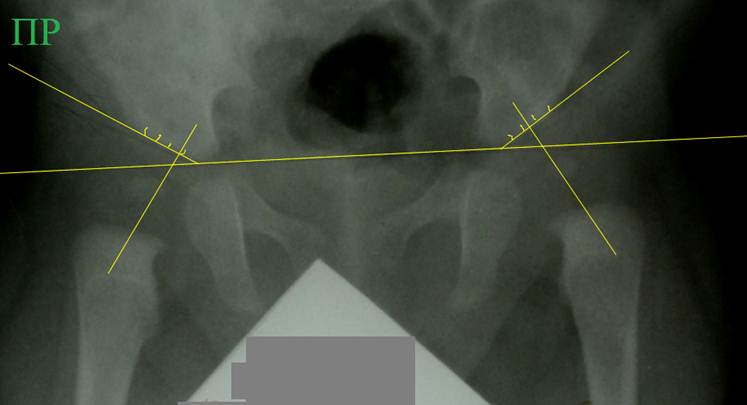

Снимок

того же ребенка, что в предыдущем примере. Выполнено расчерчивание по схеме

Садофьевой. Справа ось головки пересекает линию крыши во второй четверти, что

относится к норме. Слева ось головки

пересекла линию крыши в третьей четверти, что свидетельствует о дисплазии

сустава. Рисунок отчетливо демонстрирует недостаток схемы, связанный с

трудностью правильного проведения оси шейки бедра. Схема крайне чувствительна к правильности

укладки.